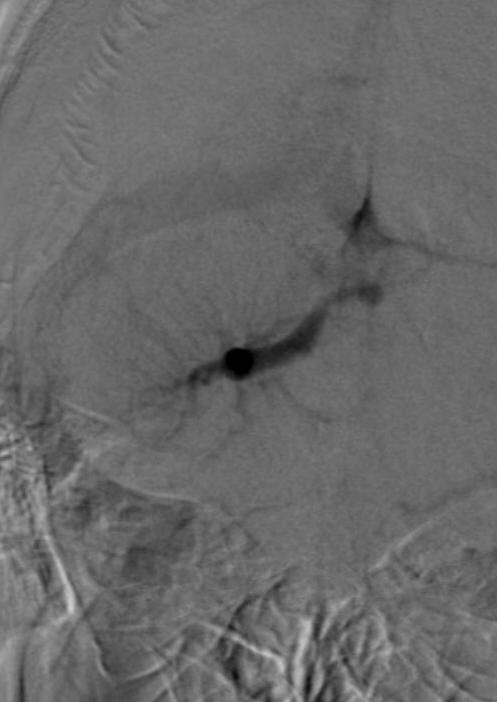

病例4